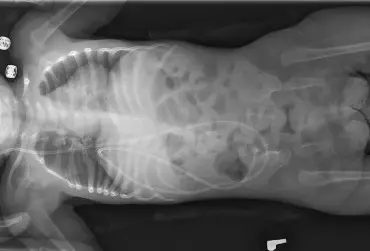

Mózgowe porażenie dziecięce - wyzwania i nadzieje

Zgodnie z definicją Baxtera i wsp. (2005) [1] mózgowe porażenie dziecięce (MPD) stanowi grupę zaburzeń rozwoju ruchu i postawy wpływających na ograniczenie aktywności. Są one spowodowane niepostępującym uszkodzeniem rozwijającego się mózgu płodu lub niemowlęcia. Zaburzeniom ruchu często towarzyszą zaburzenia czucia, poznawcze, porozumiewania się, postrzegania, zachowania oraz padaczka.

Metoda Vojty w leczeniu przepukliny oponowo-rdzeniowej

W leczeniu przepukliny oponowo-rdzeniowej bardzo istotne jest jak najszybsze rozpoczęcie terapii i pobudzenie procesów kompensacji oraz wykorzystanie możliwości adaptacji organizmu do zaburzeń czynności. Zastosowanie metody Vojty pozwala odbudować drogi nerwowe i uzyskać prawidłowy wzorzec ruchowy. Jest to metoda tania, wszechstronna i skuteczna, przede wszystkim stosowana przy czynnym udziale rodziców i w rodzinnym domu, co ma dodatkowe korzyści, jeżeli chodzi o rozwój osobowości dziecka.